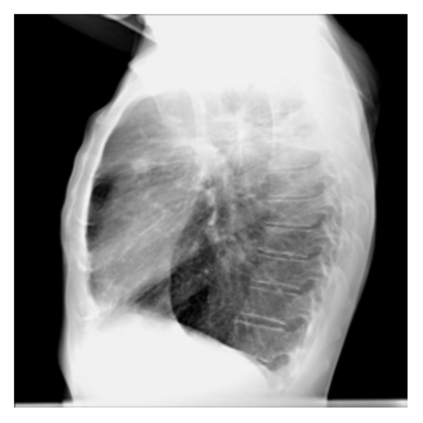

The evaluation of infectious disease processes on radiologic images is an important and challenging task in medical image analysis. Pulmonary infections can often be best imaged and evaluated through computed tomography (CT) scans, which are often not available in low-resource environments and difficult to obtain for critically ill patients. On the other hand, X-ray, a different type of imaging procedure, is inexpensive, often available at the bedside and more widely available, but offers a simpler, two dimensional image. We show that by relying on a model that learns to generate CT images from X-rays synthetically, we can improve the automatic disease classification accuracy and provide clinicians with a different look at the pulmonary disease process. Specifically, we investigate Tuberculosis (TB), a deadly bacterial infectious disease that predominantly affects the lungs, but also other organ systems. We show that relying on synthetically generated CT improves TB identification by 7.50% and distinguishes TB properties up to 12.16% better than the X-ray baseline.